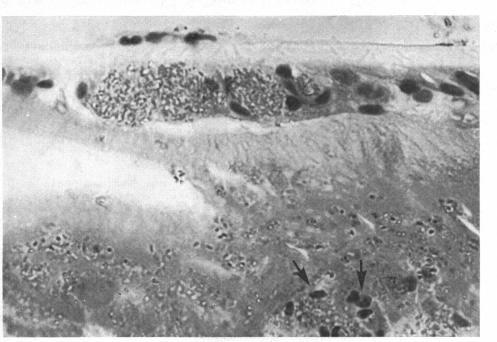

Encephalitozoonosis (nosematosis) causing bilateral cataract in a rabbit.

Bilateral cataract due to a microsporidan believed to be Encephalitozoon cuniculi (also called Nosema cuniculi) is described as an incidental finding in a laboratory rabbit. The route of infection and the significance of the findings are discussed. This is apparently the first report of cataract due to this cause.